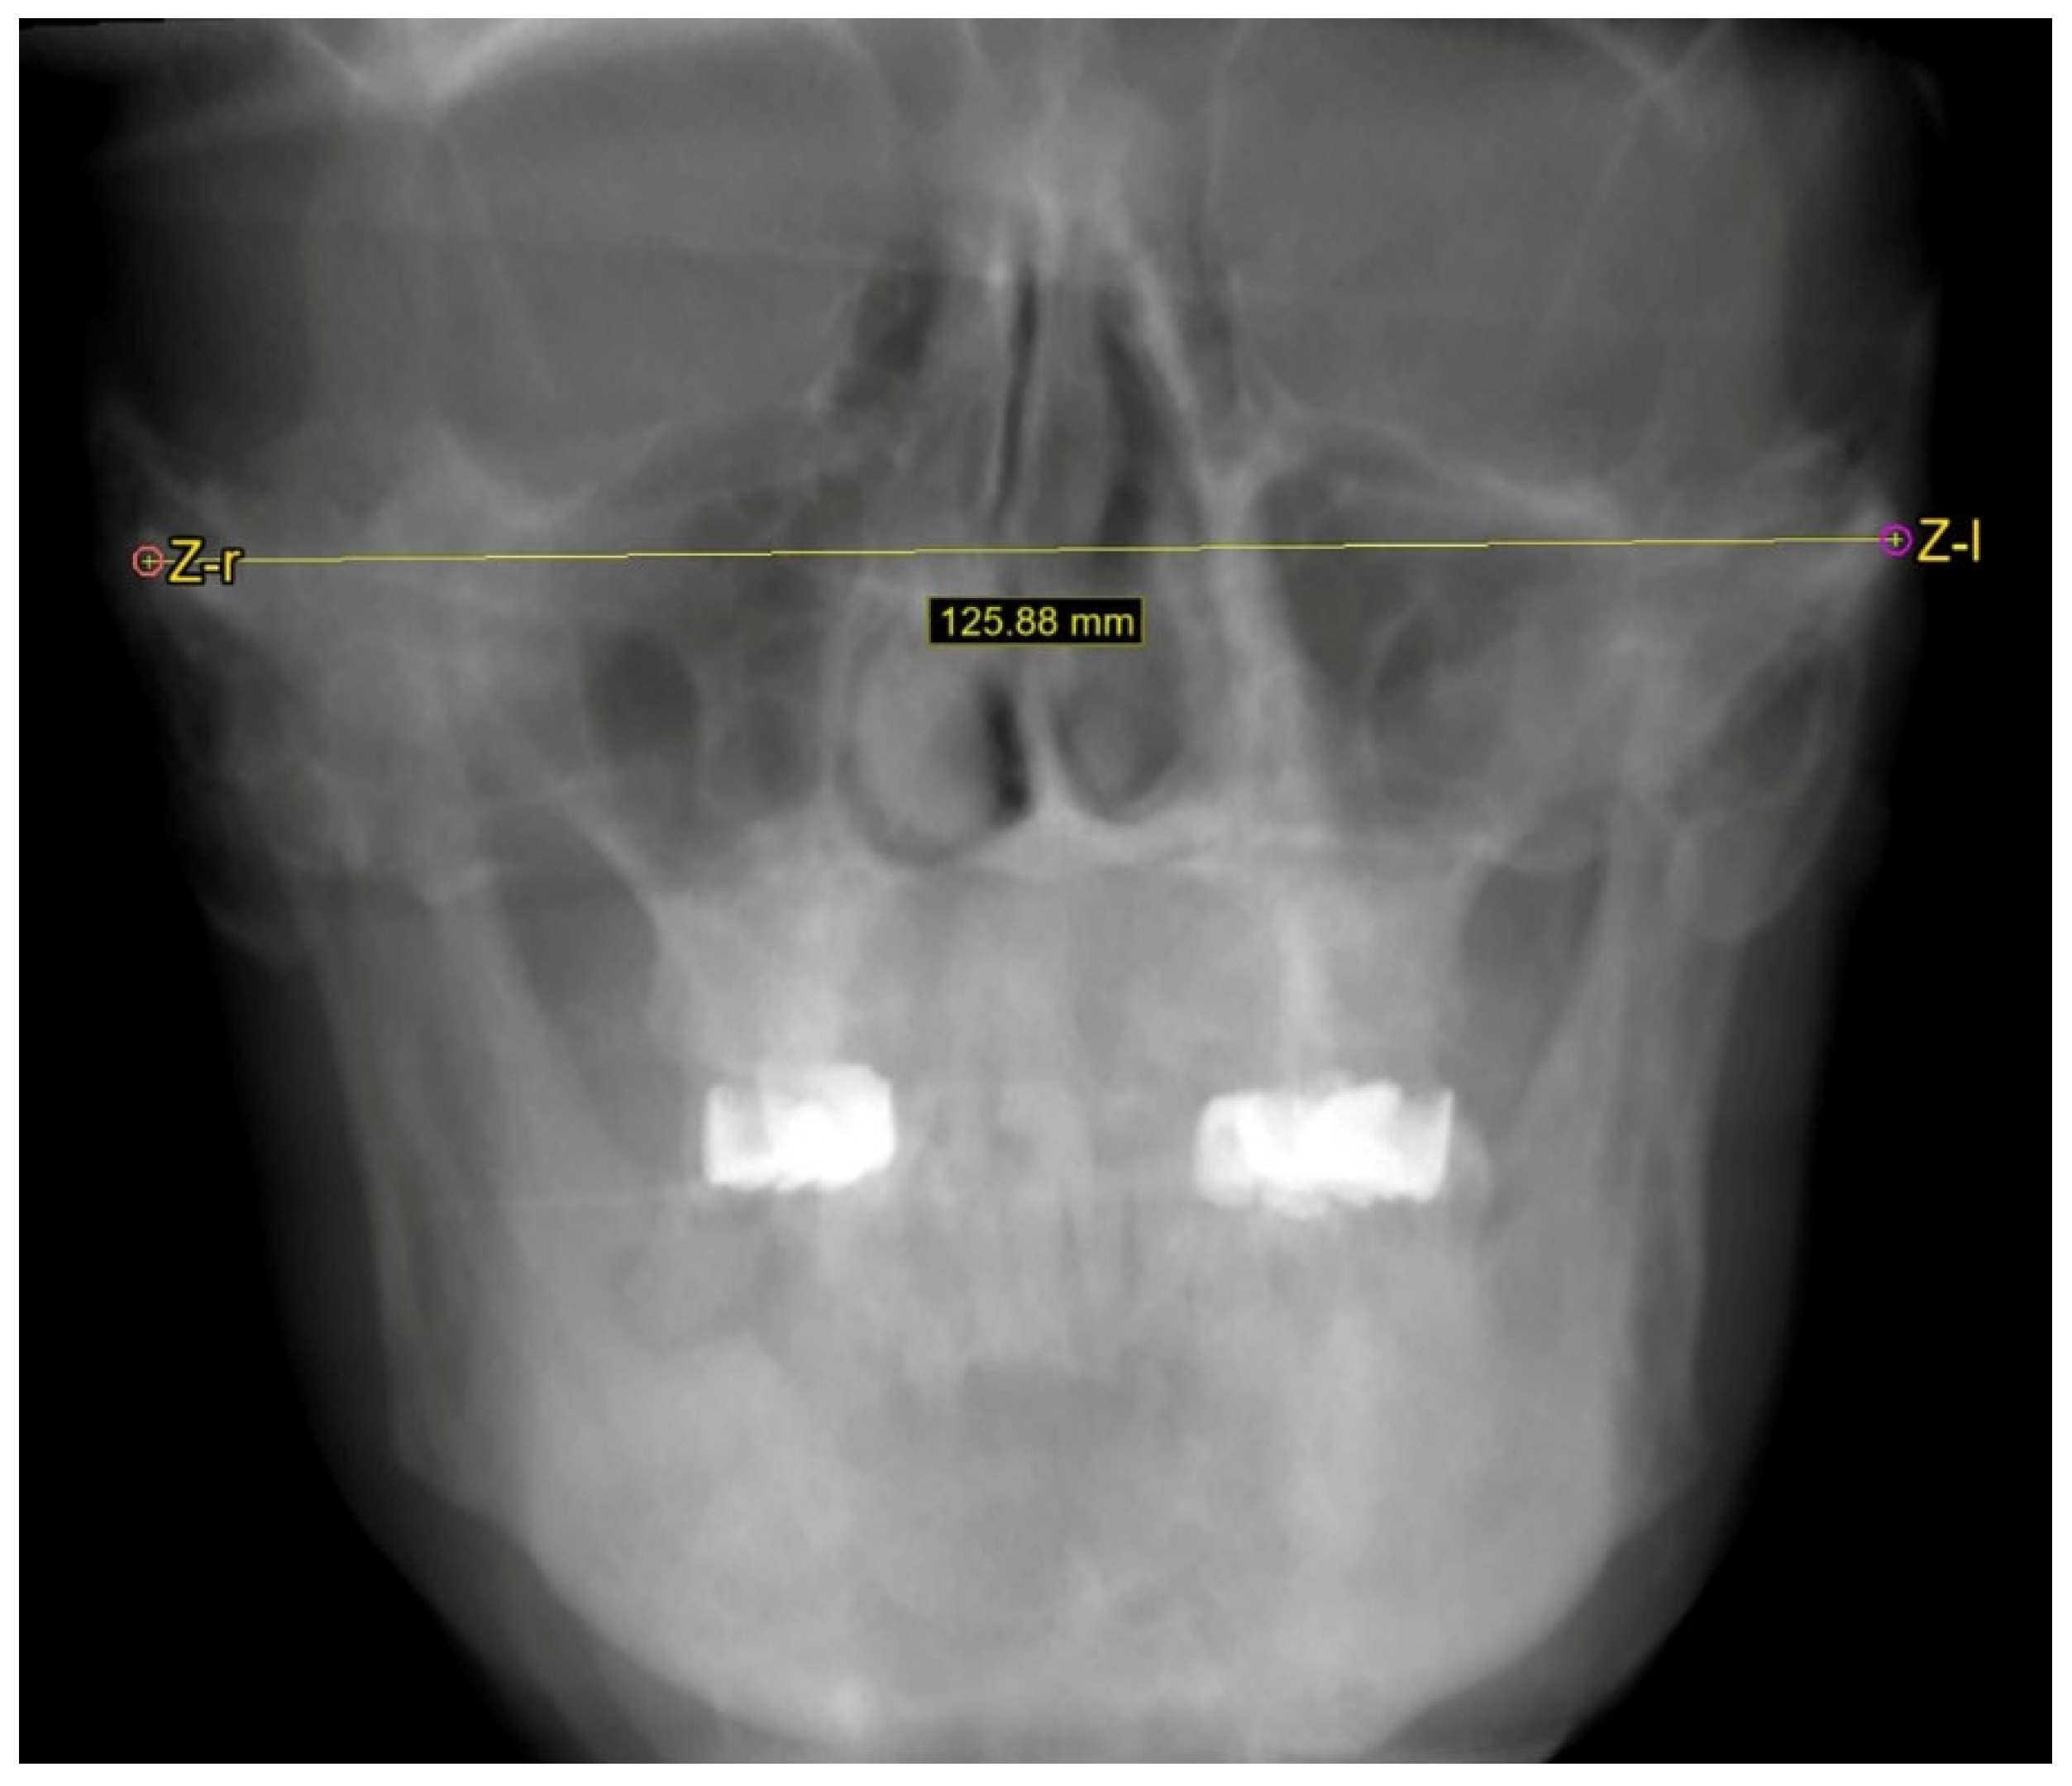

2.2. Cephalometric Measurements

3.2.1. Facial Width